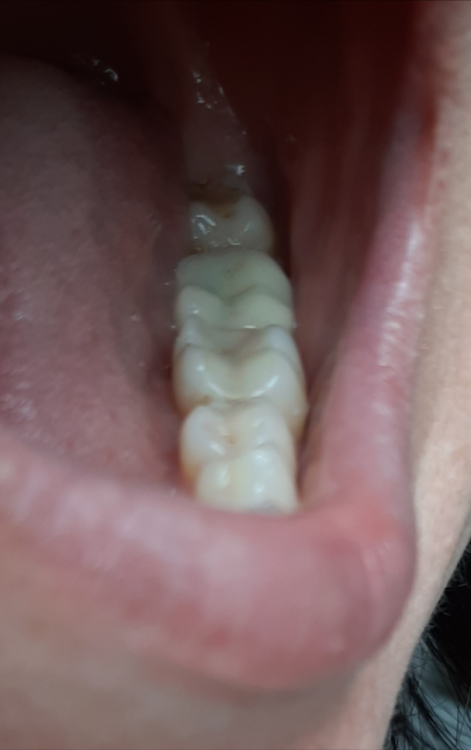

Лана-Лана Опубликовано 1 октября, 2021 Поделиться Опубликовано 1 октября, 2021 Добрый день уважаемые врачи, это опять я с продолжением темы, не знаю как лучше продолжать старую или начать новую тема( заранее извиняюсь) . Поставили мне коронку ( 7ка), при примерке я сразу обратила внимание что коронка ниже чем мои зубы, вернее бугры очень низкие и плоские , зуб практически как пенек, но ортопед сказал что у меня так и был свой видимо низкий , посмотрела на слепки и там все хорошо с этой коронкой. Я доверилась врачу, установили. Но дома я положила на зуб тонкую атласную ленту закрыла рот и она вытащилась ..ещё более менее на контакте с шестеркой а на контакте с восьмым зубом ну практически около десны..и теперь при жевании твердого немного больно десну в той области где коронка совсем низкая. Сказать что я расстроилась ничего не сказать, коронка цирконевая дорогая, что за криворукие техники... Что теперь делать? Может зуб чуть поднимется? Оцените если можно по фото...прилагаю так же снимки до депульпации зуба и после ,видно что он практически одного размера по высоте с другими зубами. И ещё момент в моем случае так неизбежна была вкладка? Почему врач всегда настаивает на вкладке? У меня что сильное разрушение зуба? Штифт ни как не хочет ставить. Цена то в два раза дороже выходит . Ссылка на комментарий

Лана-Лана Опубликовано 1 октября, 2021 Автор Поделиться Опубликовано 1 октября, 2021 (изменено) Это другой был зуб...так контакта нет с соседнем зубом и пища набивается, форма да не нравилась но я с этим смирилась и благо не в зоне улыбки!!! здесь другая проблема нет контакта с верхними зубами, и очень низкий и больно десну когда что то твердое попадает.. Как бы за 30 т за коронку ждёшь более лучшего результата и более точного исполнения ... Изменено 1 октября, 2021 пользователем Лана-Лана Ссылка на комментарий

Лана-Лана Опубликовано 1 октября, 2021 Автор Поделиться Опубликовано 1 октября, 2021 Ещё вопрос второй, по моим фото - это вообще коронка CAD/CAM стоит? Почитала что такие коронки вытачивает компьютер и очень точно , и что то я засомневалась теперь те ли коронки мне поставили..даже анотомических бугорков нет, это все врач в течении часа во рту после установки там подпиливала что бы она не была пеньком... Ссылка на комментарий